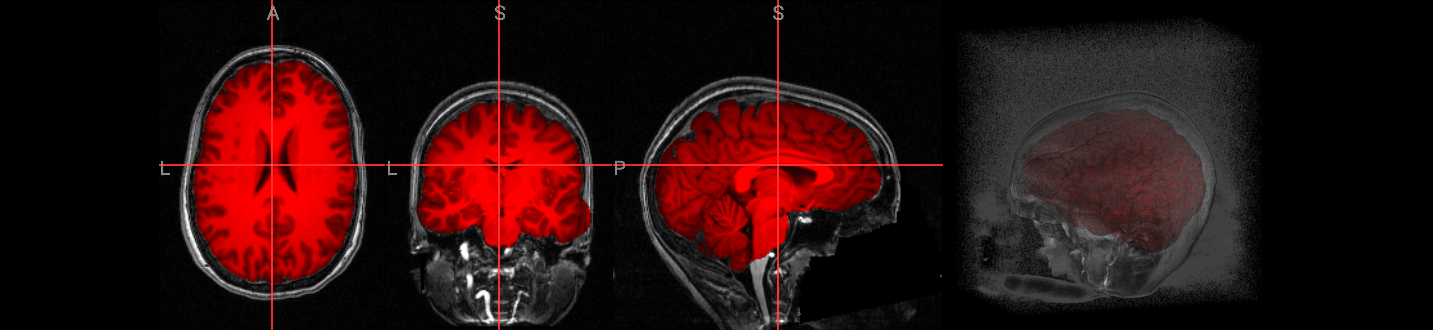

The simplest way to run 3dSkullStrip is by using the -input option to specify the anatomical dataset for processing. The -prefix option is also used to output a NIfTI image for visualization with ipyniivue.

!3dSkullStrip -input $anat_image -prefix anat_ss.nii.gz

volumes = [{"path": anat_image},

{"path": "./anat_ss.nii.gz", "colormap": "red"}]

nv = NiiVue()

nv.load_volumes(volumes)

nv

Image(url='https://raw.githubusercontent.com/NeuroDesk/example-notebooks/refs/heads/main/books/images/afni_preproc_anat_ss.png')